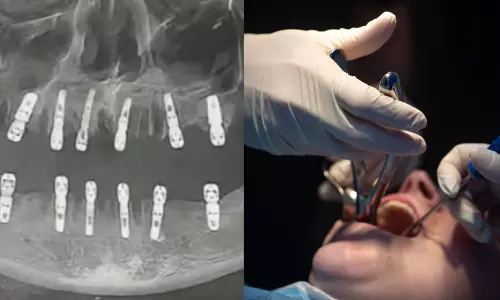

- அறுவை சிகிச்சையின்போது அவரின் 23 பற்களும் பிடுங்கப்பட்டு அதே நாளில் 12 புதிய பற்கள் இம்பிளாட் செய்யப்பட்டுள்ளது.

சீனாவில் ஒரே நாளில் 23 பற்களும் பிடுங்கப்பட்ட நபர் மாரடைப்பால் உயிரிழந்த சம்பவம் அரங்கேறியுள்ளது. சீனாவின் ஜெய்ஜியாங் [Zhejiang] பிராந்தியத்தில் உள்ள ஜின்ஹுவா [Jinhua] நகரில் உள்ள யோங்காங் டேவே Yongkang Deway பல் மருத்துவமனையில் கடந்த ஆகஸ்ட் 19 ஆம் தேதி ஹூவாங் [Huang] என்ற நபருக்கு மாற்று பற்கள் பொருத்தும் இம்பிளான்ட் அறுவை சிகிச்சையானது நடத்தப்பட்டுள்ளது.

அறுவை சிகிச்சையின்போது அவரின் 23 பற்களும் பிடுங்கப்பட்டு அதே நாளில் 12 புதிய பற்கள் இம்மீடியேட் ரெஸ்டோரேஷன் [Immediate restoration] முறை இம்பிளாட் செய்யப்பட்டுள்ளது. இந்நிலையில் மருத்துவமனையிலிருந்து திரும்பிய அவர் இரண்டு வாரங்கள் கழித்து ஆகஸ்ட் 28 ஆம் தேதி திடீர் மாரடைப்பால் உயிரிழந்துள்ளார். இதுதொடர்பாக அவரது மகள் கடந்த சமூக வலைதளத்தில் தெரிவித்ததை அடுத்து இந்த சம்பவம் வெளிச்சத்துக்கு வந்துள்ளது. உயிழந்தவரின் வயது வெளிப்படுத்தப்படவில்லை.

இதுதொடர்பாக அந்த மருத்துவமனை நிர்வாகத்திடம் விசாரணை நடத்தப்பட்டு வரும் நிலையில் ஒரே நாளில் 23 பற்களும் பிடுங்கப்படுவது குறித்து சமூக வலைத்தளங்களில் பலர் தங்களது அதிர்ச்சியை வெளிப்படுத்தி வருகின்றனர். இது அறுவை சிகிச்சை என்பதை விட எதோ வினோதமான மருத்துவ எக்ஸ்பெரிமெண்ட் போல உள்ளது என்று பலர் கூறியுள்ளனர். மேலும் ஒரே நாளில் 10 பற்கள் பிடுங்கப்படுவதே அதிகம் என்று பல் மருத்துவர்கள் தங்களின் அபிப்பிராயங்களைக் கூறி வருகிறனர்.